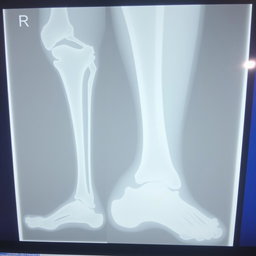

"Make medical report for leg fracture of patient, heading hospital name " national medical college hospital" hospital address: birgunj with given patient details name "Prabesh Kumar Sah" Age "18" and sex "male""